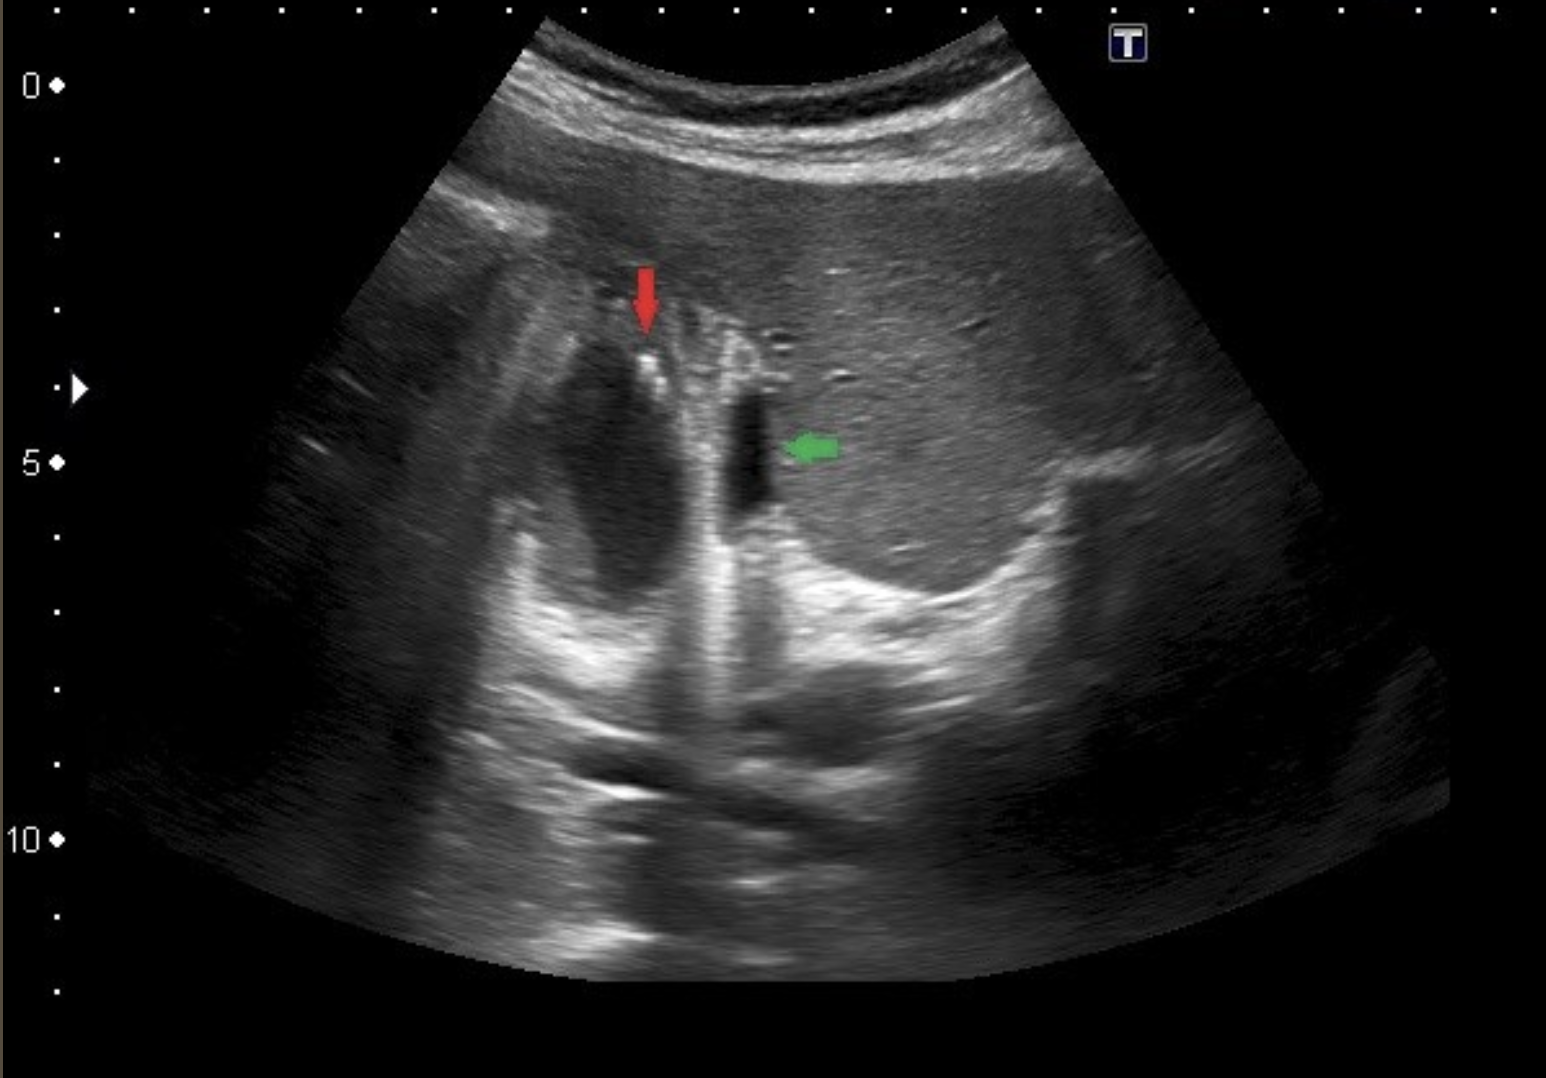

Choledocholithiasis → stones in biliary tree

clinical hx: 5 Fs → same as cholelithiasis since stone can travel

s/sx: jaundice, elevated bili and alk phos, constant RUQ pain, epigastric pain, fever, pancreatitis

2D US: “double barrel” sign, “too many tubes,” stone has rounded surface, highly echogenic, ± posterior shadowing, peripancreatic head edema/fluid → pancreatitis, gallstones, wall edema and distention

color doppler: may see twinkle artifact from stone

DDX: biliary sludge, cholangiocarcinoma